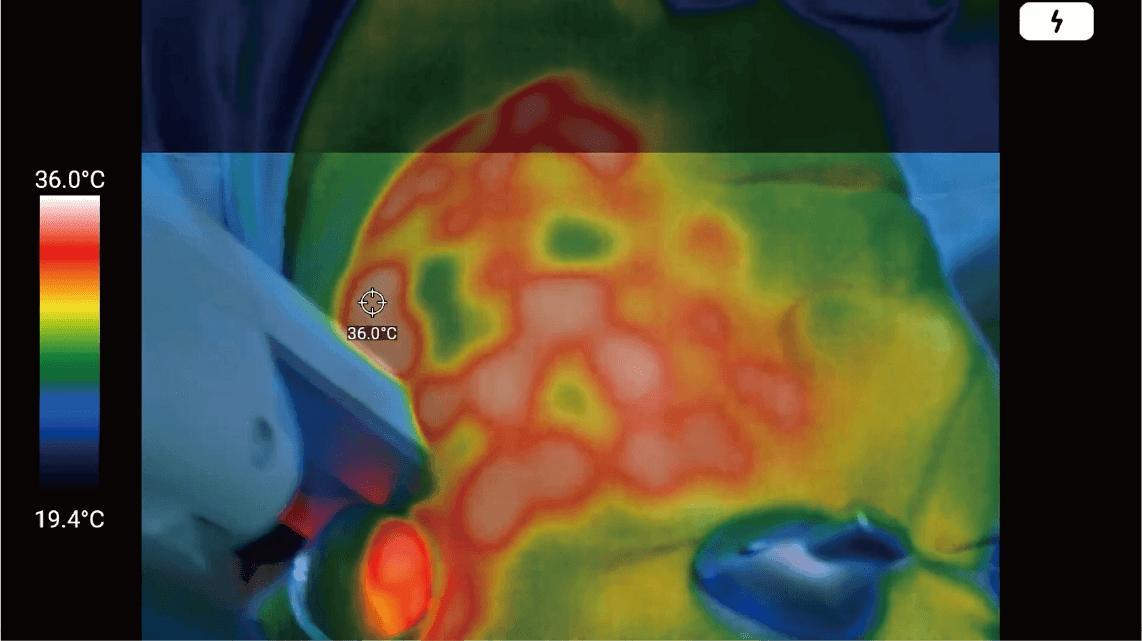

An optimal solution that enables checking the patients’ skin temperature right in front of the eye in real-time when dermatologists use heat-generating equipment such as laser or high frequency on the patients’ skin. Also, you can record and save the treatment video.

Since MetaSCOPE THERMO® accurately measures and displays changes in skin temperature in real-time, dermatologists can directly reflect changes in skin temperature during the procedure. It can recognize the highest/lowest temperature that does not cause injury leading to the maximized treatment result securing perfect patient safety. Until now, the procedure has been performed relying only on the subjective experience of the dermatologist, but now, the use of this solution can dramatically improve the procedure environment.

Prevention of injury by detailed management

of the patients’ skin temperature

(burns, frostbite, blisters, etc.)

MetaSCOPE THERMO® guarantees the accuracy of the entire procedure, including before and after the procedure, and the accuracy of the procedure related to temperature minimizes potential side effects such as burns or frostbite that may occur on the skin due to mismanagement of the temperature.